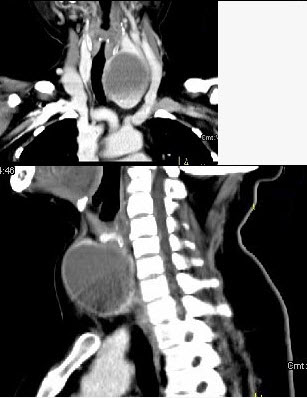

女,56岁,发现颈部肿块一月余,CT如图所示,最可能诊断为()。

A、甲状舌管囊肿

B、甲状腺乳头状癌

C、甲状腺原发淋巴瘤

D、甲状腺腺瘤

E、甲状腺脓肿

D